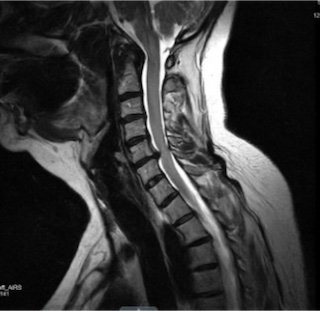

An MRI is the most common imaging study, as it shows discs, nerves, and the spinal cord in detail.

MRI scan of a human spine showing vertebrae and spinal cord.

• Not always. Many patients improve without imaging unless symptoms persist or worsen.

• Yes. Imaging findings do not always correlate perfectly with symptoms.

• Pain is influenced by inflammation, nerve sensitivity, and individual anatomy.